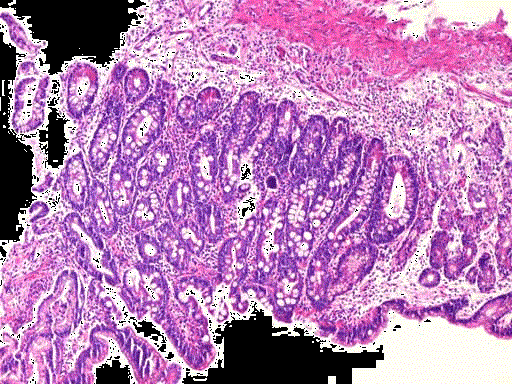

问题 胃窦部黏膜组织活检,镜下如图所示,胃黏膜发生的有关病变的描述,错误的是 ( )

选项 A.黏膜腺体中度肠上皮化生 B.这种分化上的转向,只发生于同源细胞之间 C.可分为不完全肠化和完全肠化 D.该化生对机体有利,不会发生恶变 E.该化生可恶变形成肠型腺癌

答案 D